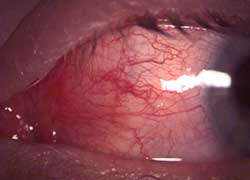

"name": "Hyperemia - Palpebral Conjunctiva",

"detail": "<h2>Symptoms</h2>\n\n<ul>\n\t<li>Typically none. May have some level of mild discomfort if associated with other lid changes</li>\n</ul>\n\n<h2>Signs</h2>\n\n<ul>\n\t<li>Engorgement of palpebral blood vessels observed on lid eversion</li>\n\t<li>Small papillae may also be observed</li>\n</ul>\n\n<h2>Etiology</h2>\n\n<ul>\n\t<li>Low grade inflammation of palpebral conjunctiva</li>\n\t<li>Often a precursor to CLPC</li>\n\t<li>May be a response to care regimen or deposition on contact lens</li>\n</ul>\n\n<h2>Prevalence</h2>\n\n<ul>\n\t<li>Mild degrees are common. Severe degrees are infrequent</li>\n</ul>\n\n<h2>Differential Diagnosis</h2>\n\n<ul>\n\t<li><a href=\"/condition/38\">CLPC / GPC</a></li>\n\t<li>See: <a href=\"/condition/64\">Palpebral Conjunctival Inflammation &ndash; Differential Diagnosis</a></li>\n</ul>\n\n<h2>Management</h2>\n\n<ul>\n\t<li>Consider changing solution from preserved multipurpose solution to peroxide based solutions</li>\n\t<li>Refit with lenses of lower modulus and improved surface wettability</li>\n\t<li>Reinforce compliance with lens replacement interval, maintenance and wearing time</li>\n</ul>",